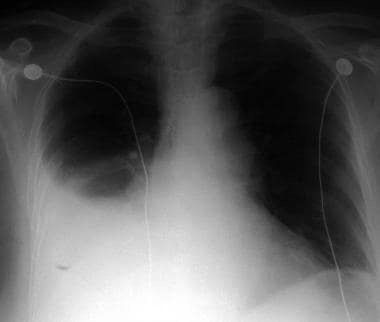

Q.6. What's the CXR finding?

Correct Answer : B